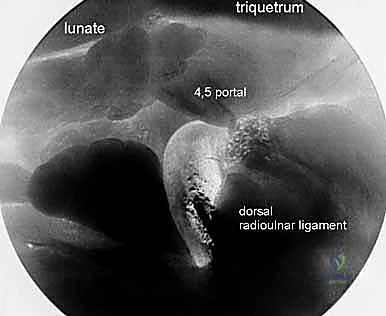

2. The Midcarpal Ulnar Portal (MCU)

- Location: Similarly located 1 to 2 cm distal to the 4-5 portal. It is bounded by the EDC and the EDM tendons.

- Anatomy: Enters the midcarpal joint, providing views of the lunotriquetral articulation, hamate, and capitate.

- Neurovascular Risks: The dorsal cutaneous branch of the ulnar nerve is at risk here.

- Function: Complements the midcarpal radial portal for triangulation, allowing instrumentation for débridement, loose body removal, or chondroplasty.

3. The Triquetrohamate Portal (T-H)

- Location: Enters the midcarpal joint at the level of the triquetrohamate joint, ulnar to the ECU tendon. Its entry site is both ulnar and distal to the midcarpal ulnar portal.

- Anatomy: Directly accesses the articulation between the triquetrum and hamate.

- Neurovascular Risks: Branches of the dorsal cutaneous branch of the ulnar nerve are most at risk here.

- Function: A special-use portal for specific pathology localized to the triquetrohamate joint.